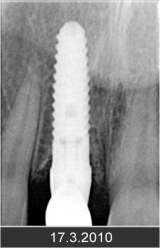

• Zavedení implantátu do kosti čelisti

• Zahojení do kosti – 3-4měsíce(v některých případech i déle – doplňování kosti)

Zavedení implantátů do kosti je většinou ambulantní chirurgický výkon, srovnatelný s vytržením zubu a většinou se provádí v lokální anestézii. Ve výjimečných případech je možné použít i analgosedaci či celkovou narkózu. Operaci provádí zubní lékař-implantolog při dodržení všech podmínek sterility pro operaci. Nástroje pro tuto operaci jsou konstruovány tak, aby výkon byl šetrný vůči kosti a zavedení implantátu bylo provedeno ve velmi krátké době. Díky kvalitní anestézii je výkon nebolestivý. Aby byl pooperační otok co nejmenší, je potřeba operovanou oblast chladit, dle poučení ošetřujícího lékaře. Lékař také ordinuje podle potřeby léky na bolest, případně antibiotika.

Průměrná doba hojení implantátů před provedením definitivního protetického ošetření je 3-4 měsíce, v případech, kde je nutné doplnit chybějící kost (různé metody, postupy a materiály) – tzv. augmentace) se může doba hojení prodloužit na 8-12 měsíců. S tím je pacient vždy předem seznámen svým lékařem.